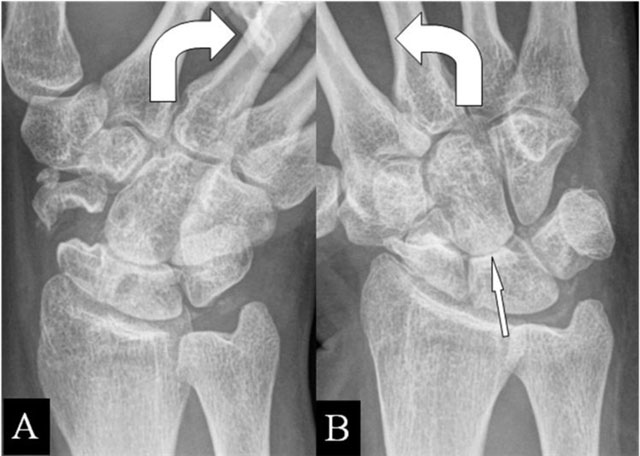

(Intra)scaphoid abutment

Fractures appear most frequently at the scaphoid waist [14]. Radial deviation gives an impaction at a pseudarthrosis. Contact zone deformation (Figure 6A and B) and mobility between the fragments are illustrated on radiographs. BMO and extrinsic ligamentous lesions are delineated by MRI.

Figure 6

(Intra)scaphoid abutment. (A, B) PA plain mobility radiographs in ulnar and radial deviation. (A) Large diastasis in ulnar deviation between the scaphoid bone fragments. (B) Impaction of both fragments in radial deviation. Associated midcarpal osteoarthritis (arrow).